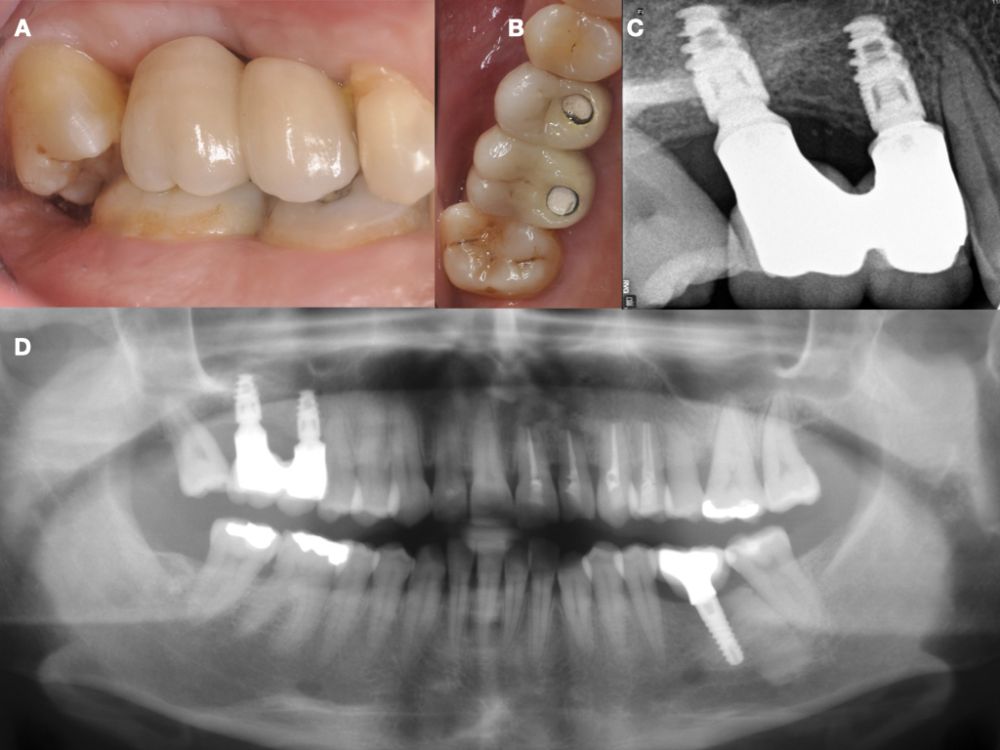

Seis meses tras la cirugía de elevación de seno maxilar se realizó la reentrada para la colocación de implantes. Se obtuvo una biopsia de tejido óseo de 3 x 7 mm mediante trefina y se solicitó un análisis histomorfométrico, obteniendo un 30,56% de hueso vital (Figura 7). Tras la muestra para la biopsia se colocaron dos implantes bone level Naturactis de ETK® (ETK Implants S.L, Sant Boi de Llobregat, España) con un torque de inserción de 35 Ncm, comprobándose su correcta colocación en el postoperatorio inmediato mediante una radiografía periapical (Figura 8). Seis meses tras la colocación de los implantes la paciente pudo acudir a realizarse la segunda fase para colocar pilares de cicatrización, y mediante un CBCT de comprobación se valoró la altura ósea final, teniendo un incremento de 4,2 mm en la zona del 1.6, y de 6,1 mm en la zona del 1.7 (Figura 9).

Quince días después de la segunda fase se realizó la toma de impresiones para la realización de dos coronas ferulizadas cemento-atornilladas sobre bases de titanio, comprobándose el ajuste mediante una radiografía periapical paralelizada (Figura 11). Seis meses tras la colocación de la restauración se realizó una revisión clínica y radiográfica, observando el buen aspecto de los tejidos blandos (Figura 12).